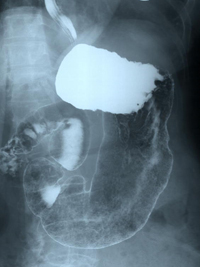

MDLを受ける方は前日の夜8時以降は絶飲食をして検査当日に胃の中を空にする必要があります。胃内に残渣物があると病変と間違われる可能性があります。検査の5分程前に、胃や腸の動きを一時的に穏やかにする注射がされます。ただし、前立腺肥大、緑内障、不整脈のある人は注射をすることが出来できない場合もあります。透視台に上がるとバリウムという造影剤と、胃を膨らせるための発泡剤という薬剤を飲んで検査を進めます。この検査では、食道がん、胃がん、胃潰瘍、胃炎、十二指腸潰瘍等及び術後の診断に用いられます。